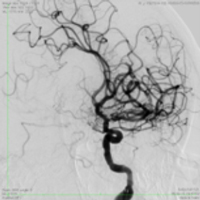

Современные технологии позволяют провести специальный инструмент в зону тромба, перекрывающего просвет артерии головного мозга, зацепить его и извлечь (рис. 2), тем самым восстановить кровоток по закрытой артерии (рис. 3).

![]() Рис.2 |

![]() Рис.3 |